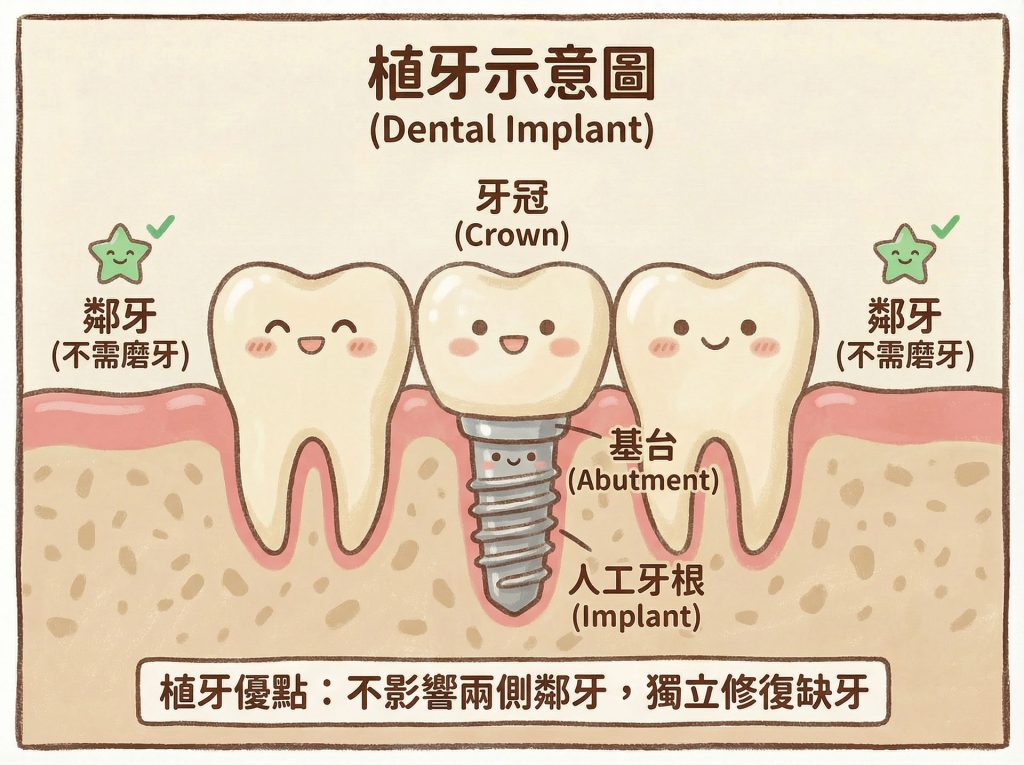

植牙跟牙橋怎麼選?先講結論:沒有絕對比較好,只有哪個更適合你的口內條件

有些案例,植牙能保留鄰牙、受力獨立、清潔更直觀;

有些案例,牙橋反而能同時保護本來就需要治療的鄰牙,整體設計更合理。

3. 力的傳導與使用需求

今天一顆牙齒就像一個工人,他只要負責他一個人承受的咬合力即可。

缺1顆牙,兩邊的工人來幫忙,2個人做3個人的工作量

→ 一個人分攤1.5份的工作量。

缺2顆牙,兩邊的工人來幫忙,也就是2個人做4個人的工作量

→ 一個人分攤2倍的工作量。

缺3顆牙,以此類推….

所以缺牙越多,對於鄰近兩顆牙的負擔就越大

長久下來這2顆牙齒不恰當的分配,恐成未來隱患。

缺牙後能不能做牙橋,從來不是只看「補不補得上」,而是要看這座橋在長期使用下,能不能承受得住。